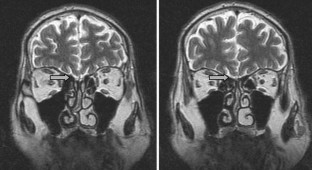

Fig. 1